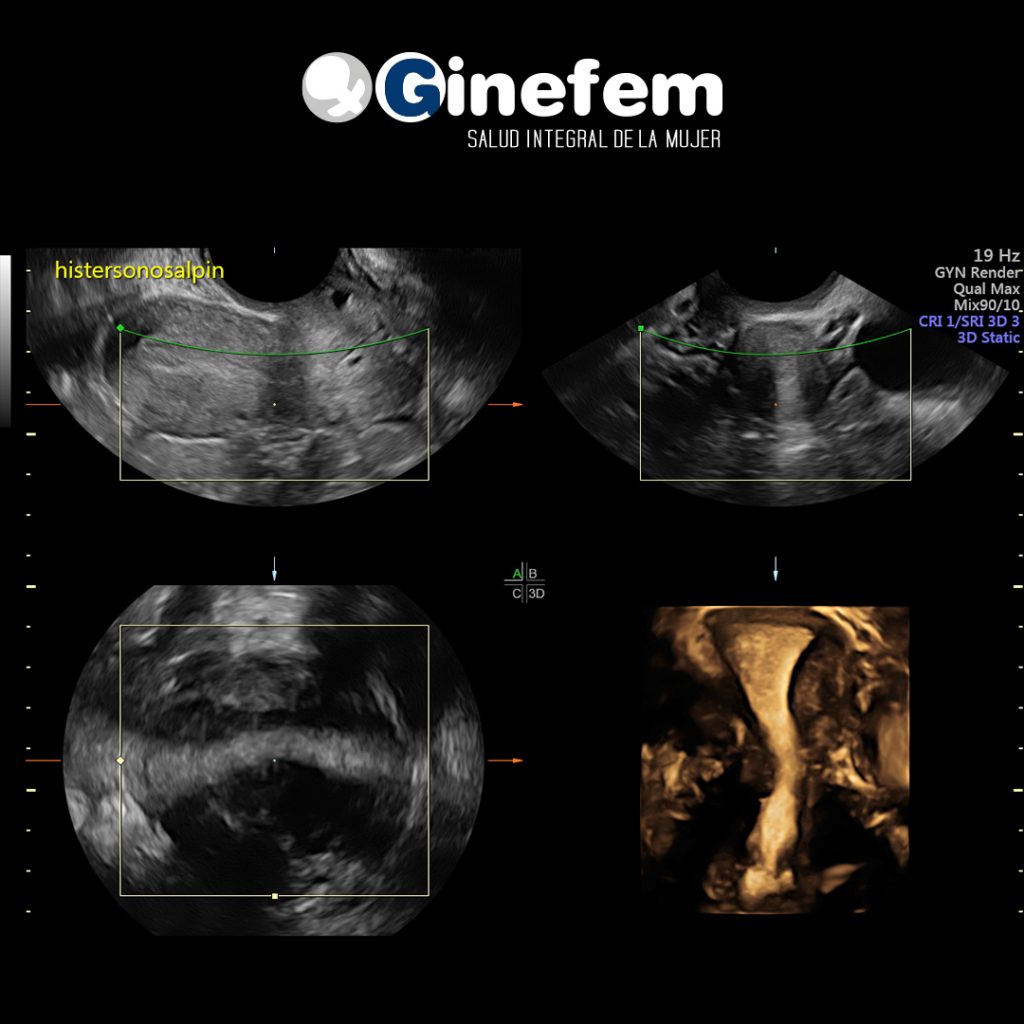

- Ecografía para valorar útero, ovarios y endometrio.